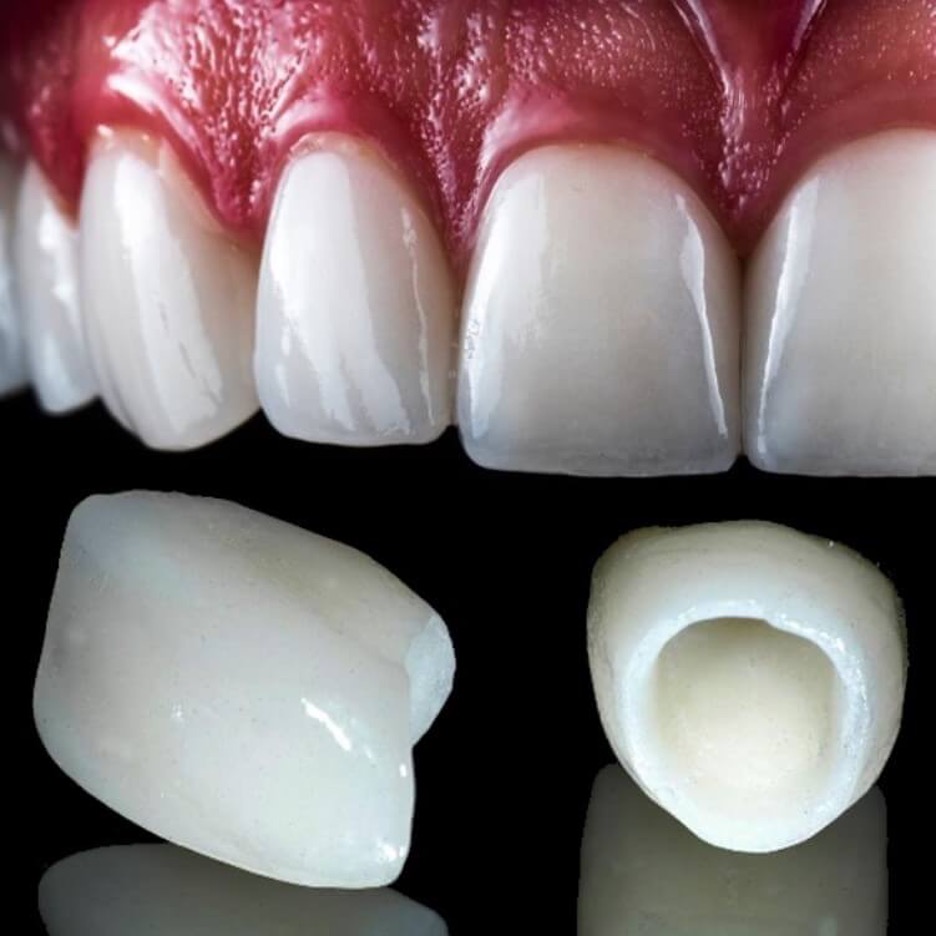

Zirconia crowns are a type of dental crown made from zirconia, a very strong and durable ceramic material known for its aesthetic qualities. They are custom-made to fit each patient's mouth and are designed to blend in naturally with the remaining teeth for the long term. They cover the damaged or decayed teeth, providing strength, functional restoration and a natural appearance.

Zirconia crowns are popular because they can withstand biting and chewing forces well, are biocompatible (unlikely to cause allergic reactions), and can be matched closely to the color of natural teeth. They are a popular choice in modern dentistry and it makes them a preferred choice for many dental patients who are seeking long-lasting natural treated tooth protection, longevity, comfortable bite and aesthetically pleasing dental restorations.

The price of a Zirconia crown in Lahore typically ranges from Rs. 30,000 to Rs.40,000 per crown in 2025. As Zirconia crowns are considered one of the best for their durability and natural look making them a top choice for patients seeking both functionality and restore beautiful smile, hence its prices are higher than other types of crowns. Most of the Government dental hospitals do not have zirconia crown facilities because they cannot afford expensive crown material. Factors that affect the variation in zirconia cost in Lahore include Quality of Zirconia: Higher-grade zirconia crowns with superior strength and aesthetic properties may cost more and the factors as discuss above.

E-max or Porcelain crowns are dental cap that cover damaged, weakened or decayed entire visible part of a tooth. They are made from porcelain, which resembles natural tooth enamel in color and translucency, making them a popular choice for restoring the appearance and function of teeth, harder than zirconia crowns, and hence they are more expensive than zirconia crowns.

They are custom-made to fit over the prepared tooth and are bonded into place by a dentist. Porcelain crowns improve the tooth's strength, shape, and overall aesthetic, making them a popular choice for patients. They are mostly use in front teeth for improvement of the aesthetics of teeth with severe discoloration or irregularities.

E-MAX crowns, made from high-quality porcelain, are generally more expensive than traditional porcelain fused to metal and zirconia crowns. The cost of an E-MAX crown in Lahore ranges from Rs. 15,000 to Rs. 50,000. For those seeking high aesthetics and a perfect match with natural teeth, E-MAX crowns are an excellent choice despite their higher price range.

Zirconia, and E-max are the best crowns and bride choice for front/anterior teeth all across the world because their shades perfectly matches the natural teeth shades. Porcelain fused to metal (PFM) is not recommended on front teeth because of the metal hue and gray gum margins as discussed above.